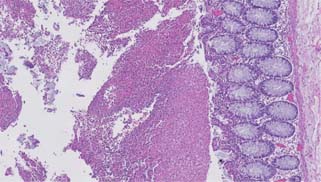

Figure 5: Medium power image of fibrinopurulent exudate, with sevelamer (left) and Kayexalate (right) crystals (Hematoxylin and eosin, 10× magnification).

These medical resins may be encountered in a colonic biopsy or resection specimen. Histologic identification may be difficult as the morphology may overlap between different resins (see Table 2 and Figures 1-8). However, once identified, these findings should be communicated to the clinical team.